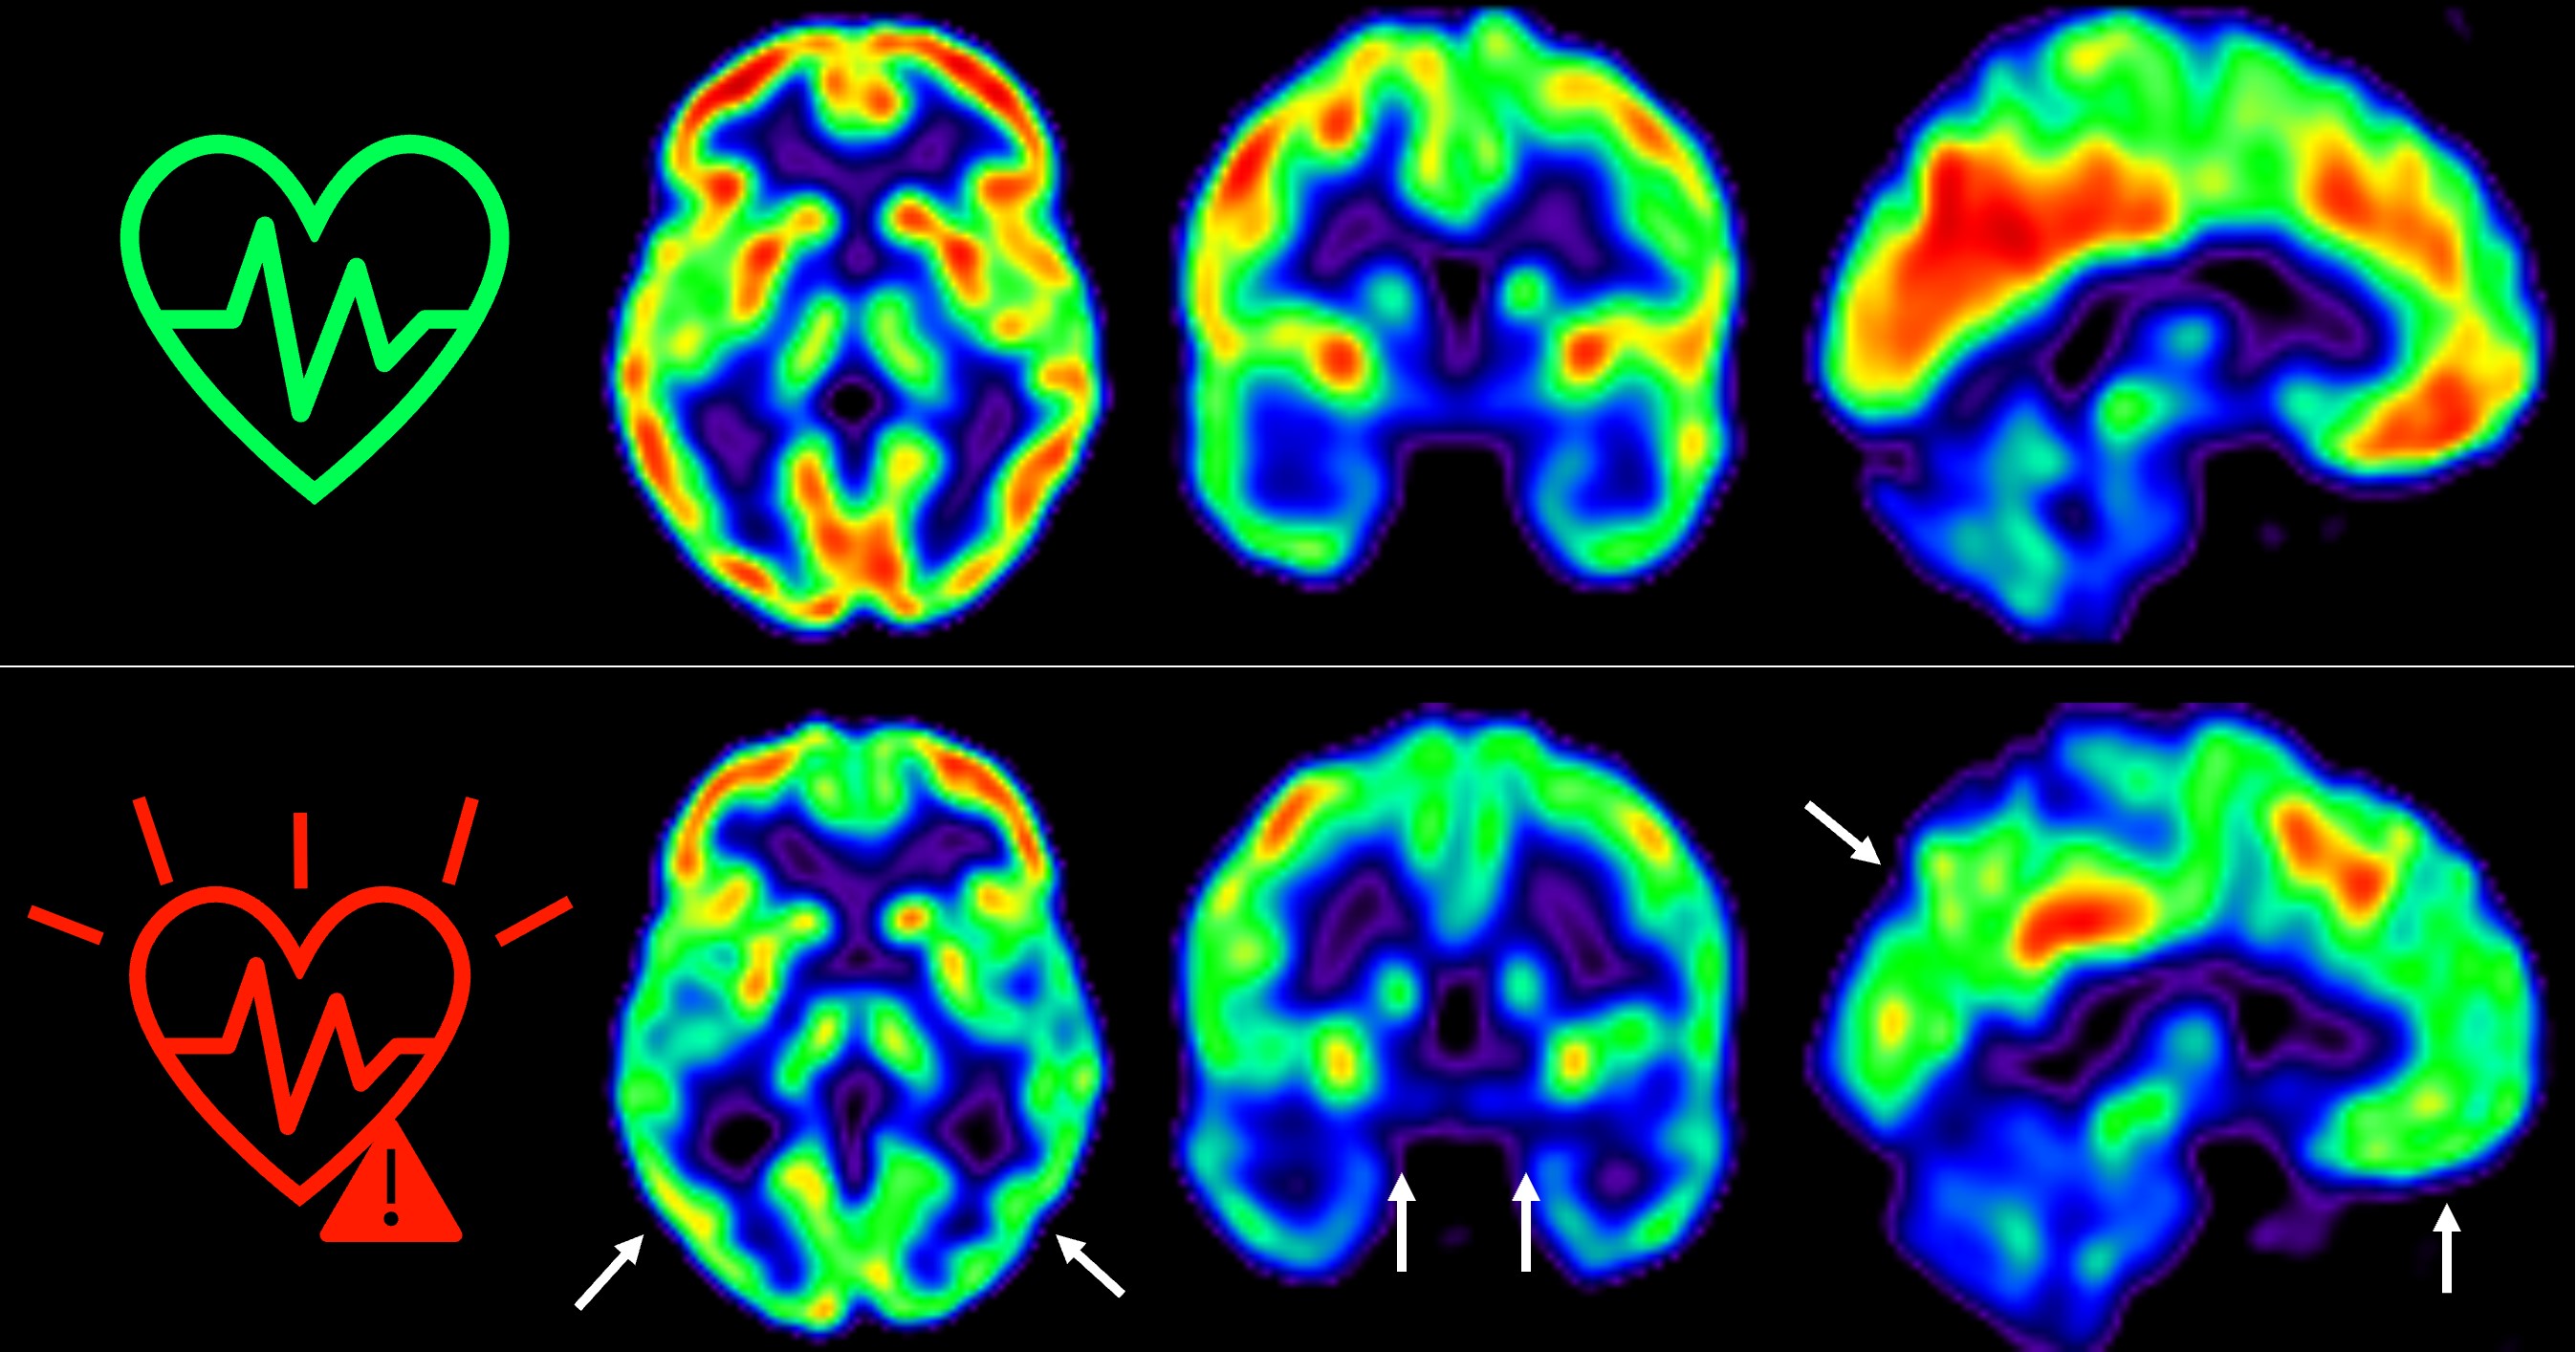

Cuanto antes empecemos a controlar los factores de riesgo cardiovascular, mejor para nuestro cerebro

Un estudio publicado en The Lancet Healthy Longevity muestra que las personas de mediana edad con un riesgo cardiovascular elevado de forma sostenida durante 5 años experimen...Hospital Universitario Fundación Jiménez Díazen/health-centers/hospital-universitario-fundacion-jimenez-diaz